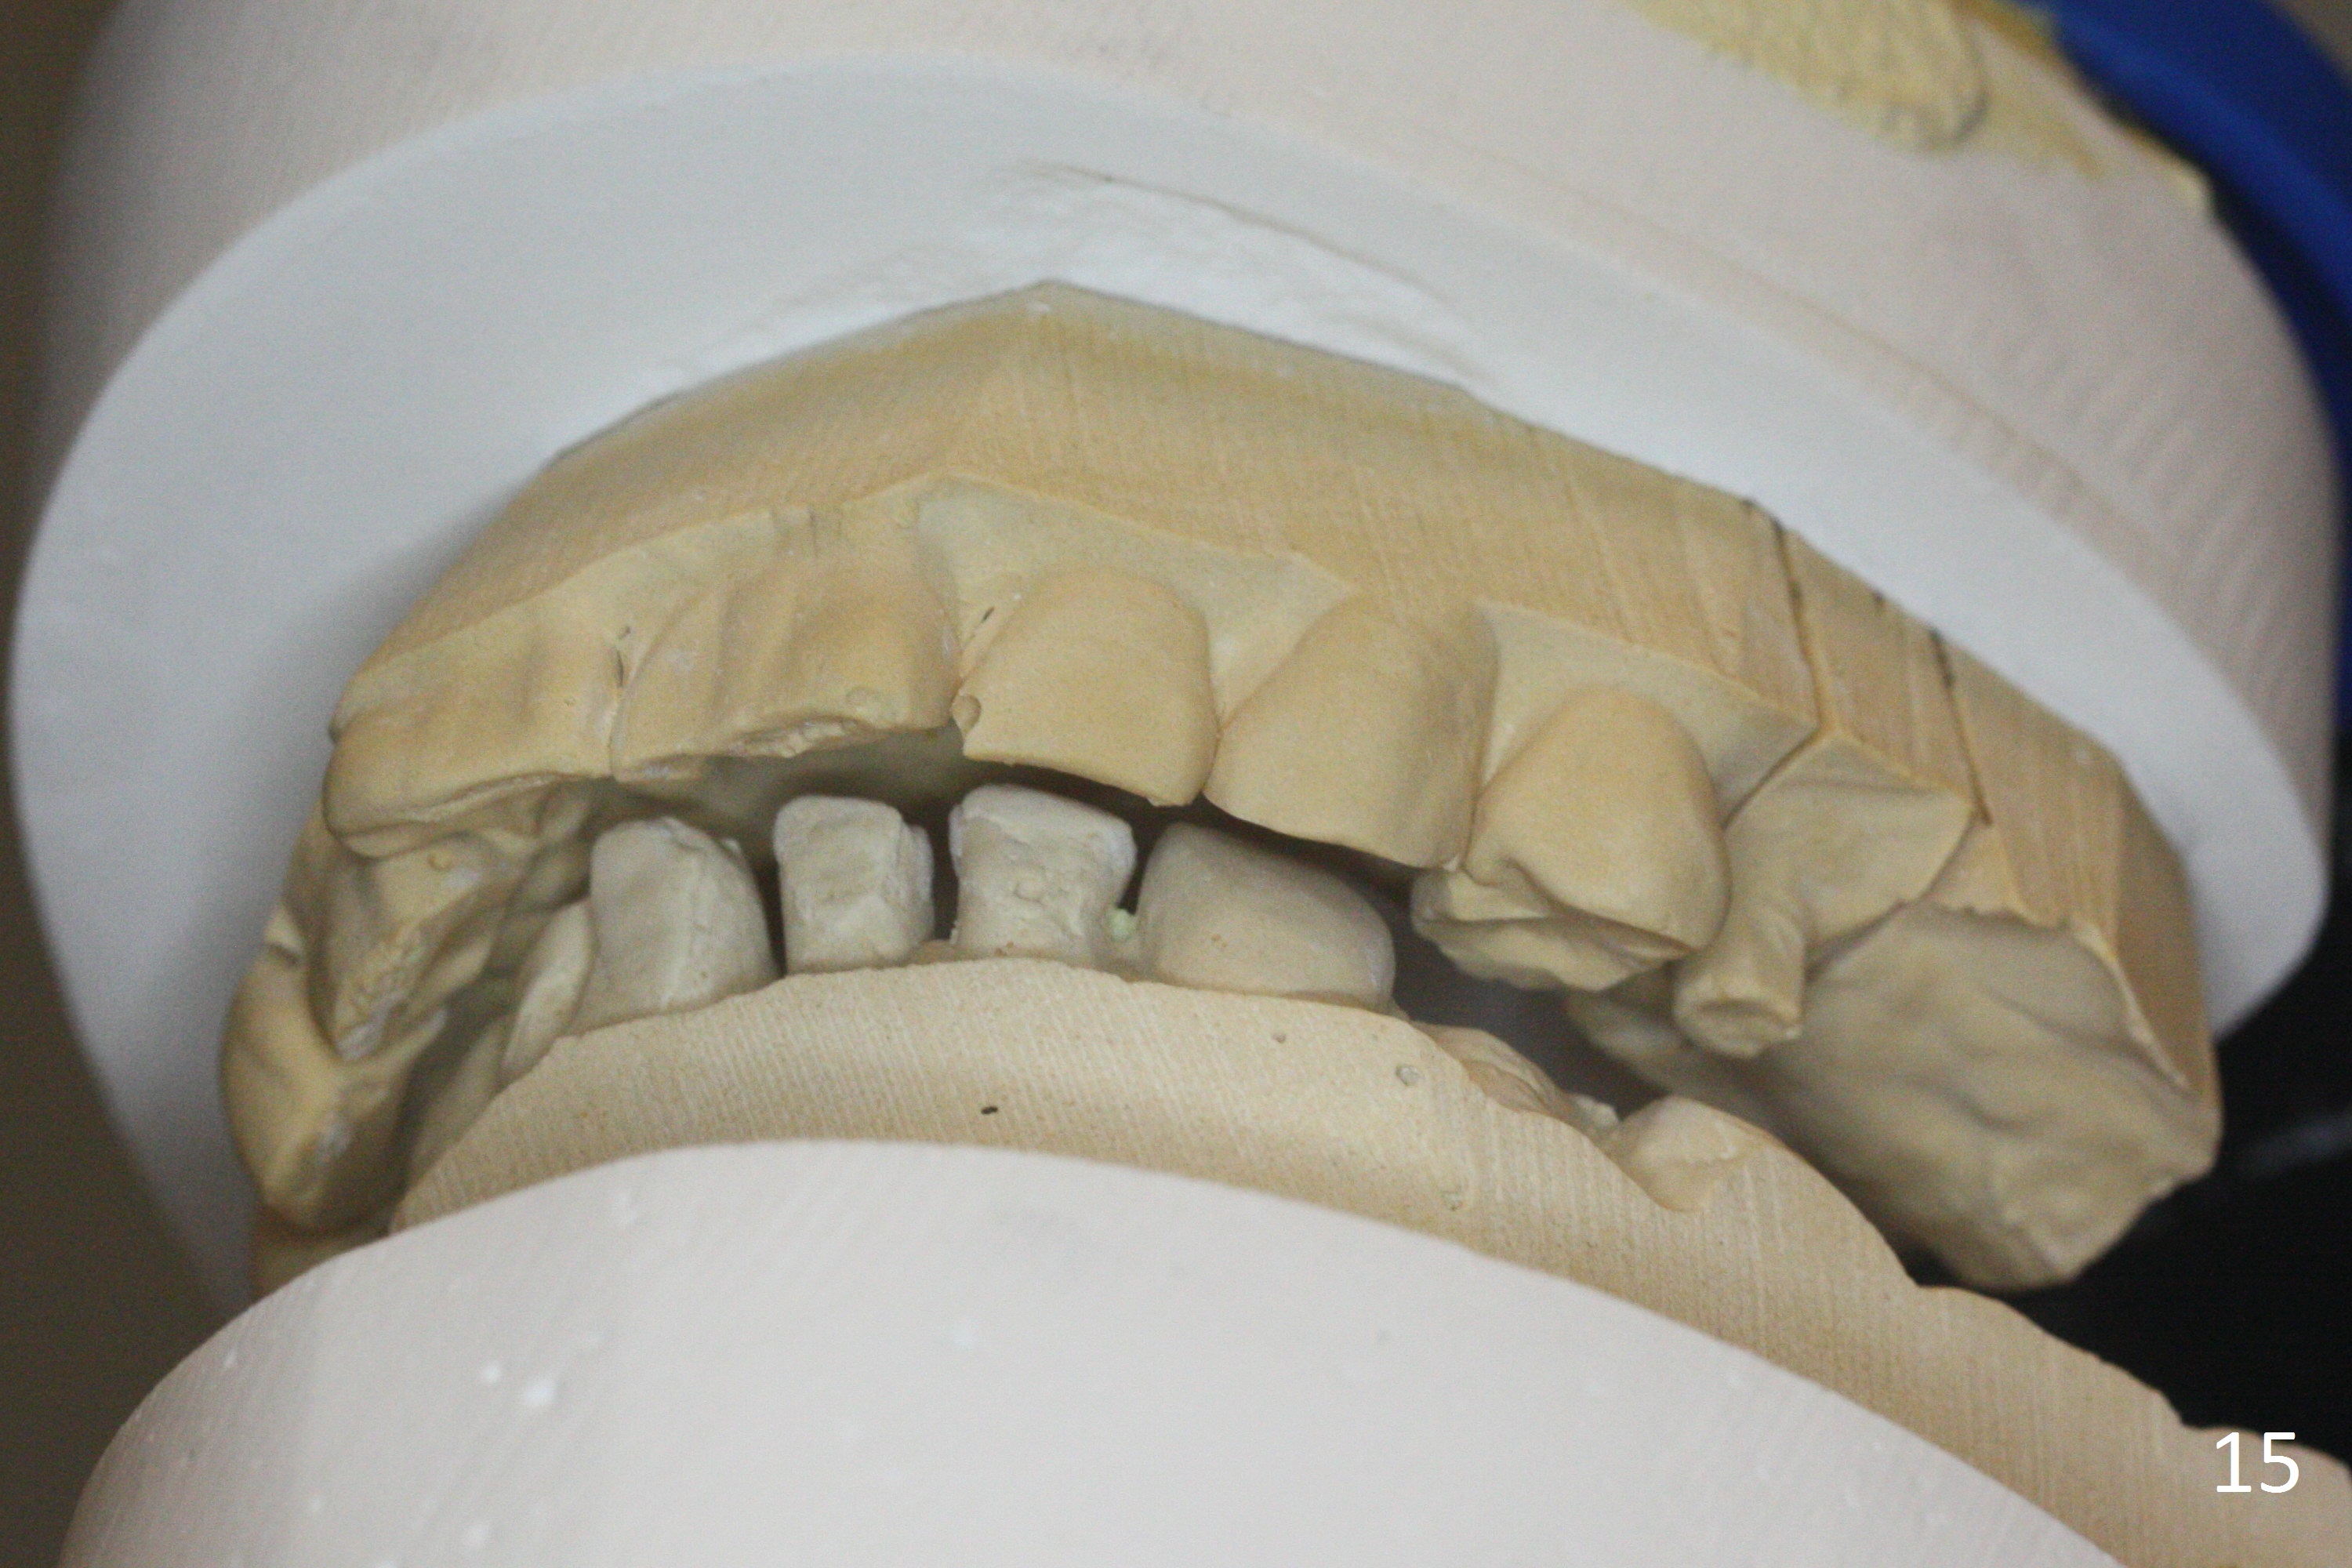

The right posterior final restorations (Fig.14) are fabricated as planned: increase in vertical height (Fig.15). The increase is minimal (Fig.14, 17(#2 limited crown height), 16 (#2 crown being thin *)). Fig.17,18 are taken immediately post cementation. There is no bone loss 10 months post cementation (Fig.19,20). The gingiva is healthy around the implant crowns (#2, 4 and 28) 1 year 4 months post cementation (Fig.21,22).